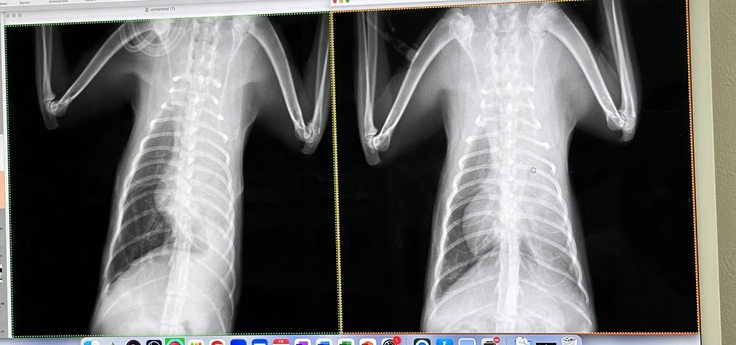

退院時にはこの先1〜2ヶ月は肺の状態をしっかり見ながら手術をしないといけないかどうか先生と一緒に判断していかないといけない状態でしたが、退院後の初めての通院検査でのレントゲンでは真っ白だった肺に酸素が入って黒く映っていました!

↑左肺真っ白の時

↓退院後。初の通院時左肺に空気が入って黒く映っています。

先生もモモの回復力にびっくりされていましたが胸水も増えていないのと後は体が吸収するのを待つという判断でしたので、手術もしなくていいと言っていただき、通院もしなくて大丈夫と判断していただけました!脅威の回復力です!